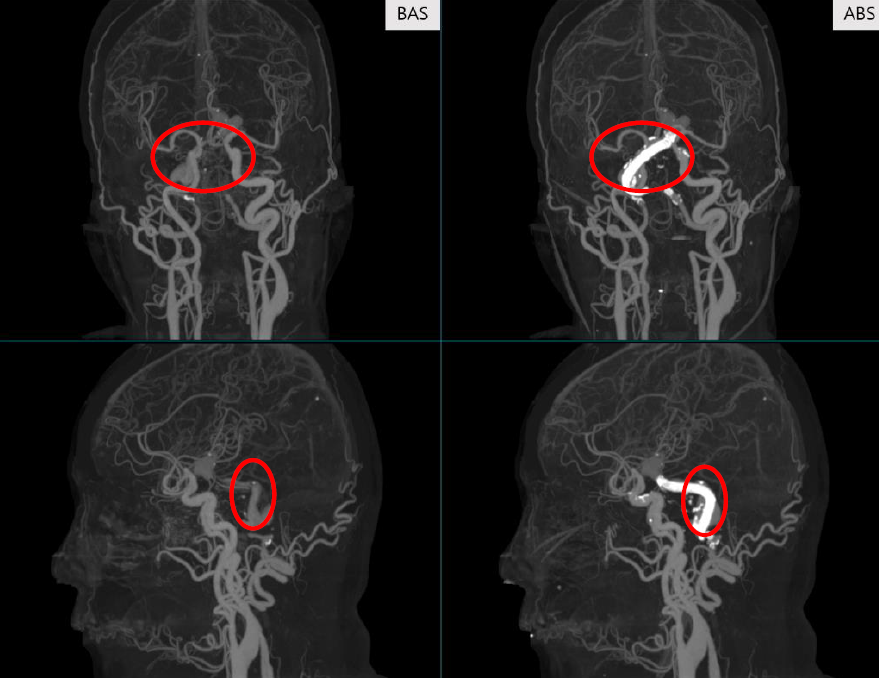

Performance comparison of BAS (left) and ABS (right).